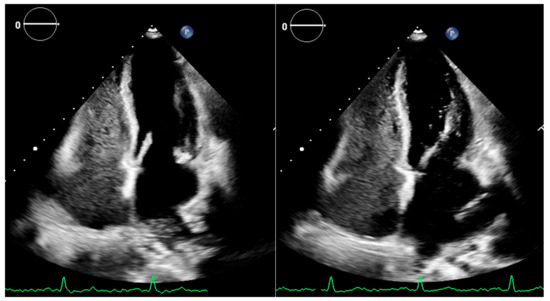

3. Cirrhotic Cardiomyopathy Diagnostic Approach with Echocardiography: Current Knowledge

4. Cirrhotic Cardiomyopathy Diagnostic Approach with Echocardiography: Future Perspectives